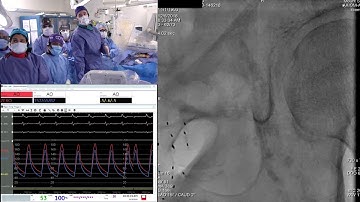

Evolut PRO Platform Case - Cusp Overlap in Small Anatomy (Skills Corner Session @EACTS 2021)